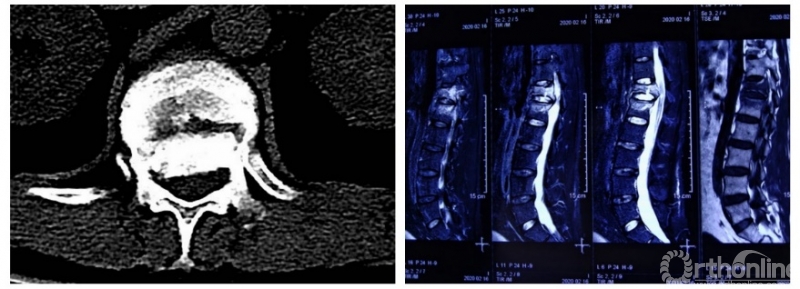

术后脊柱固定情况

2月23日,患者从ICU转入普通病房,其生命体征平稳,双下肢疼痛过敏症状明显好转,双下肢感觉功能基本恢复,双踝肌力4级,手术疗效理想。